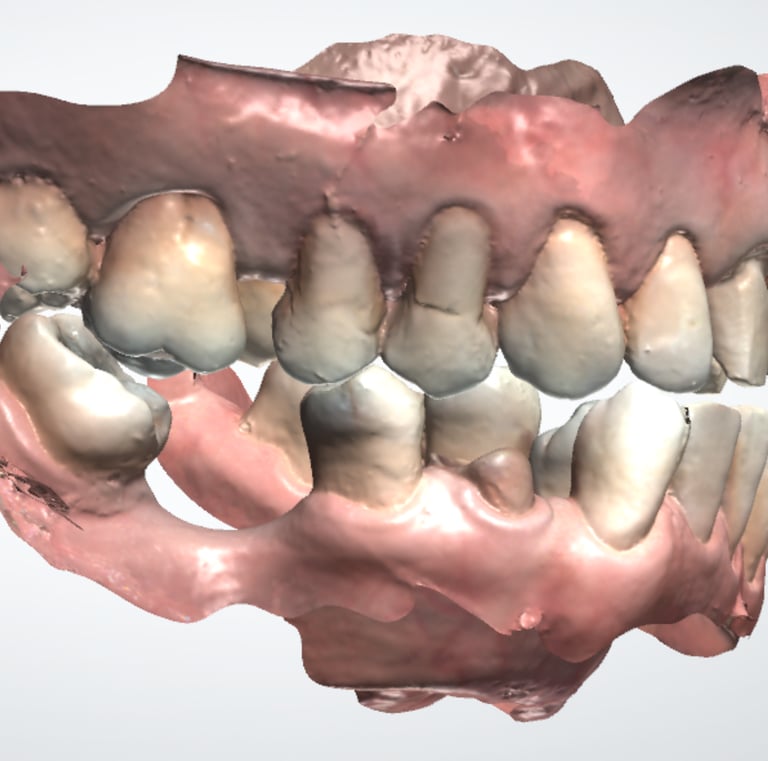

1. Registros iniciales: Modelo digital, tomografía dental y exámenes de laboratorio clínico.

2.Simulación y evaluación: Se planifica digitalmente el implante para evaluar cualquier riesgo.